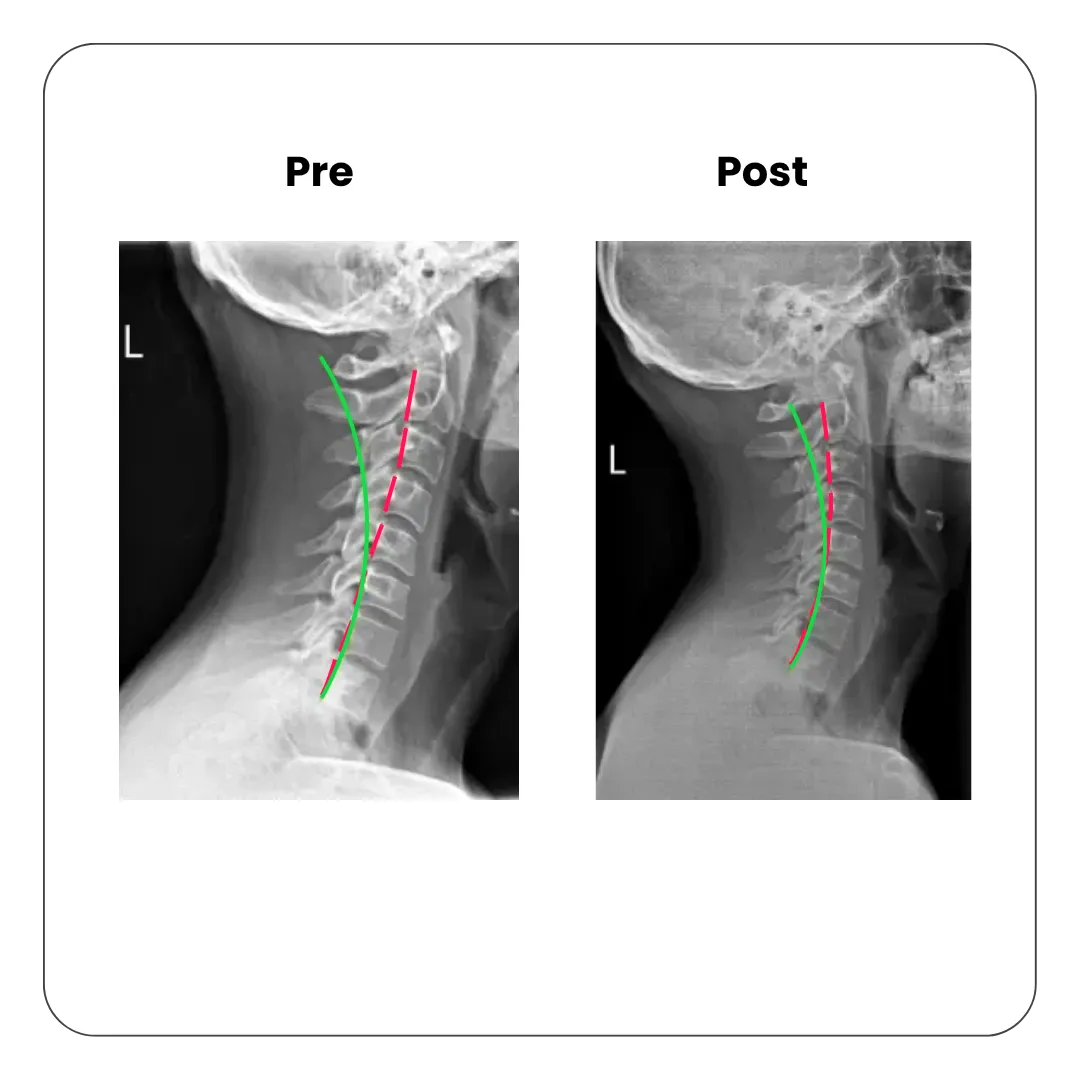

Improve the cervical curve

The cervical lordosis, or the neck’s natural curvature, can be lost over time due to an injury, poor posture or repetitive stress. Regardless, it is important to maintain that natural curve to allow for proper nerve function. SpineWorks specialises in improving the cervical curve through chiropractic adjustments, specific targeted exercises and traction. Loss of cervical curve is often the cause of chronic neck pain and headaches. It can accelerate the progression of wear and tear of the intervertebral disc, known as spondylosis.

Pre and post X-ray showing improvement in cervical spine curve after posture correction